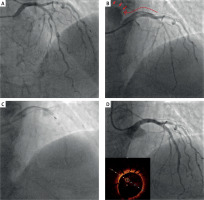

Figure 1

Angiographic sequence of iatrogenic aortocoronary dissection (IACD) management with rotational atherectomy. A – Baseline coronary angiography showing multiple lesions in the proximal and mid left anterior descending artery (LAD). B – Retrograde IACD extending from the proximal LAD to the left main coronary artery (red arrow), classified as Dunning Class II. Despite preserved distal LAD flow, no devices, including low-profile balloons, could cross the dissection plane. C – Bailout rotational atherectomy with a 1.25 mm burr using pecking-motion technique to minimize complications. D – Final angiographic result after deployment of three drug-eluting stents, with optimal stent apposition confirmed by optical coherence tomography

This case illustrates management of a rare PCI complication involving retrograde LMCA dissection with aortic extension. While conservative management may be considered for IACD, progressive dissection and symptom development necessitated immediate intervention. Given that unsuccessful stent delivery in this scenario carries significant mortality risk, bailout RA was essential for procedure completion. We selected the smallest available burr to minimize the risk of intimal flap enlargement. The RA proceeded without complications and enabled adequate stent expansion, as confirmed by optical coherence tomography. In cases where dissection sealing fails or PCI is unsuccessful with concurrent hemodynamic instability or persistent symptoms, surgical intervention should be strongly considered.